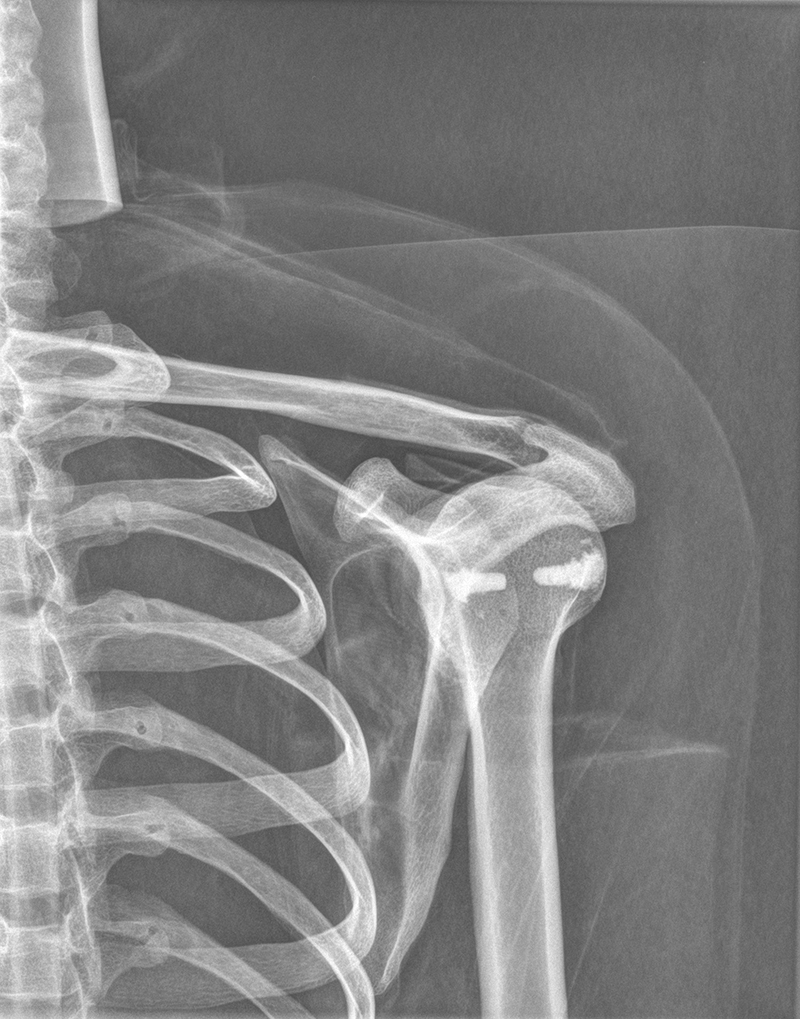

Dieses weltweit einmalige Phantom bietet erstklassige Übungsmöglichkeiten für die Lagerungs- und Einstelltechnik in der Projektions-Radiographie und gehört eigentlich zur Grundausstattung jeder Röntgen-Ausbildungsstätte. Das Phantom enthält ein natürliches menschliches Skelett sowie die Umrisse von Kehlkopf, Lunge, Herz und Nieren (Organe erscheinen als Schatten auf den Röntgenbildern), dadurch können mit dem Phantom echte Röntgenaufnahmen wie beim Patienten gemacht werden. Durch die Verwendung des echten Skeletts können Leitstrukturen im Knochen erkannt werden, was bei Kunststoffskeletten nicht möglich ist. Bei der Montage des Phantoms wird besonderer Wert auf die Darstellung der Gelenkspalte gelegt. Die Gelenke sind voll beweglich montiert, und ermöglichen die Lagerung in den normalen Röntgenpositionen (z.B. Froschposition, Pro- und Supination des Unterarms). Die Arme können nach oben bewegt werden, so dass das Modell auch für alle knöchernen Untersuchungen im CT verwendet werden kann. Bei jedem Phantom handelt es sich um ein handgefertigtes Unikat, welches sich in Größe und Ausführung unterscheiden kann. Je nach Modell können pathologische Befunde vorhanden sein, die äußere Erscheinung kann sich je nach Größe des Modells unterscheiden. Die neue Ausführung dieses Modells wurde in Zusammenarbeit mit einer namhaften deutschen Schule für Med. Techn. Radiologieassistenten komplett überarbeitet und erfüllt alle Anforderungen für die Ausbildung. Der Verkauf dieses Phantoms erfolgt nur gegen Nachweis der medizinischen Verwendung. Natürliche Größe.